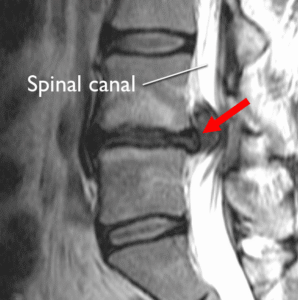

Как изглежда дисковата херния на MRI

MRI е едно от най-често използваните образни изследвания, когато трябва да се оцени състоянието на междупрешленните дискове и нервните структури. В MRI описанията често могат да се срещнат термини като:

дегенерация на диска

булджинг диск

дискова протрузия

дискова екструзия

секвестрация

притискане на нервно коренче

стеснение на гръбначния канал

фораминална стеноза

Образното изследване може да даде важна информация за формата на диска, неговата височина, наличието на издуване или херниране, както и за евентуален контакт с нервни структури. Въпреки това MRI трябва винаги да се разглежда заедно със симптомите и функционалната оценка на пациента.